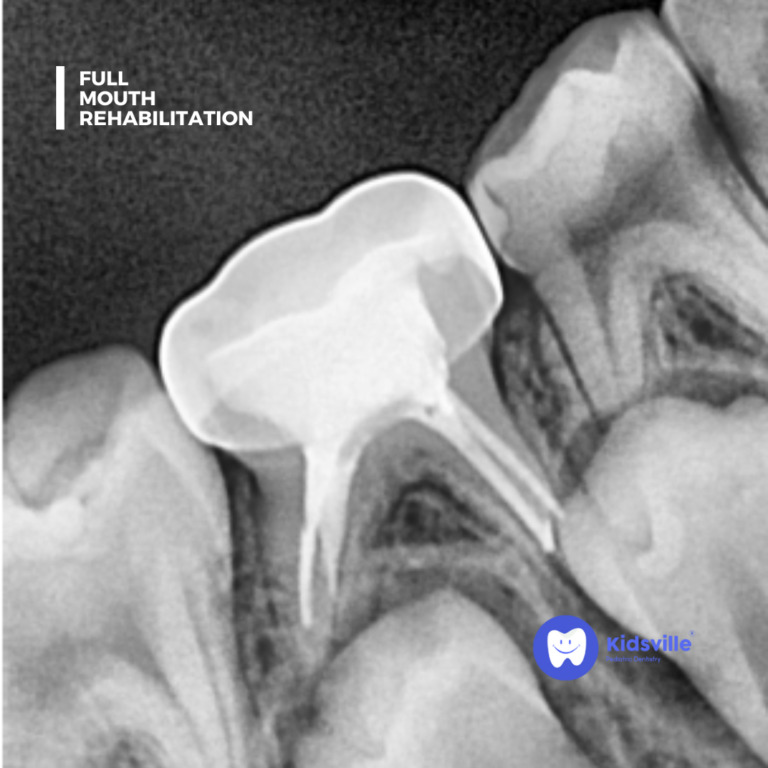

A thorough examination and diagnostic tests (such as digital X-rays) to assess the condition of all teeth and gums.

Root Canal Treatment (RCT)

For saving severely decayed or infected teeth.